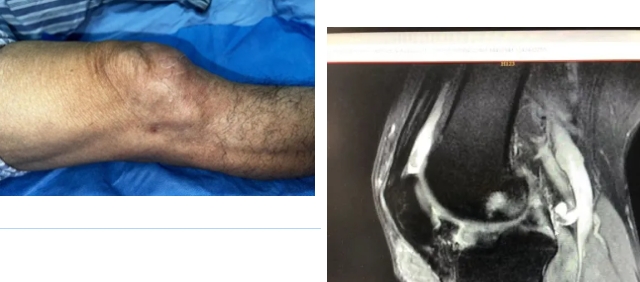

当各位痛风老铁们看到以下图片时

您会不会怕自己的膝关节

也会变成这样呢?

这些都是痛风放任不管

尿酸长期失控可能带来的影响

患者马某(化姓)有多年痛风病史,因长期未规范服药,且忽视饮食、作息管理,近一年感觉双膝关节疼痛加重,关节伸直及屈曲活动受限,并经常有卡压感。随后,马某慕名前往我院运动医学专家熊志主任医师门诊就诊。经详细询问病史、细致体格检查后,熊志明确病情,为其制定右膝关节镜下关节清理微创手术方案。手术全程顺利,成功取出痛风石游离体。术后,患者恢复情况良好,已顺利出院,膝关节功能逐步改善。

尿酸是肝脏代谢产生的废物,需经肾脏分解后排出体外。当饮食不当、生活习惯紊乱时,会引发嘌呤代谢异常——一方面导致肝脏生成的尿酸远超正常水平,另一方面肾脏排泄能力有限,过剩的尿酸便会从血液中析出。这些析出的尿酸盐会沉积在关节、肾脏、心脑血管等关键部位,进而诱发痛风、肾功能不全、冠心病等多种疾病。若尿酸水平长期偏高,沉积在关节周围的尿酸盐会持续压迫骨骼,不仅会造成关节软骨磨损、骨质破坏,还可能在关节内形成痛风石等游离体,导致关节卡压、活动受限,严重影响肢体功能。

各位痛风老铁务必牢记:“上医治未病”,预防就是最好的治疗,一定要积极控制尿酸,谨记“三多三少”,多出汗、多喝水、多吃碱性食物。少喝酒、少吃海鲜、少吃动物内脏。贪食贪饮前不妨想想,若自己的关节真变成前面图片里的样子,到时再后悔可就晚了,所以有痛风的老铁们千万记得正规服药降尿酸,同时管好饮食、注意休息,千万别熬夜。